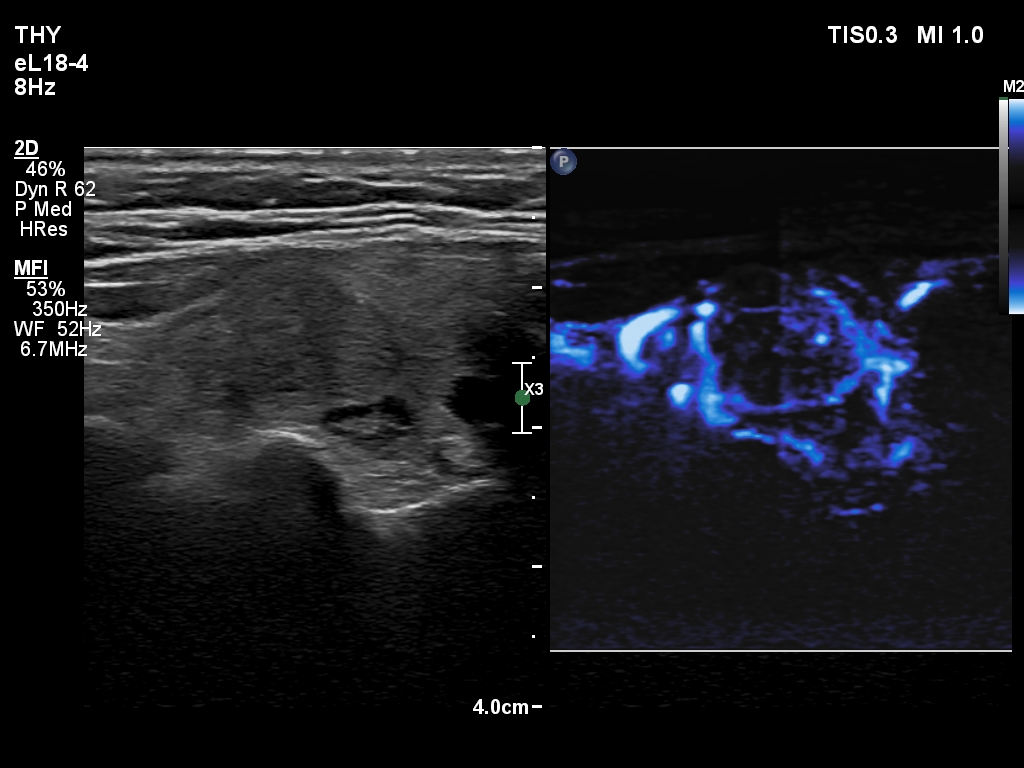

The composition of the nodule - case 2179 (ultrasonographic picture 19)

Right lobe, longitudinal scan

Middle-lower part of the left lobe, transverse scan, microflow imaging.